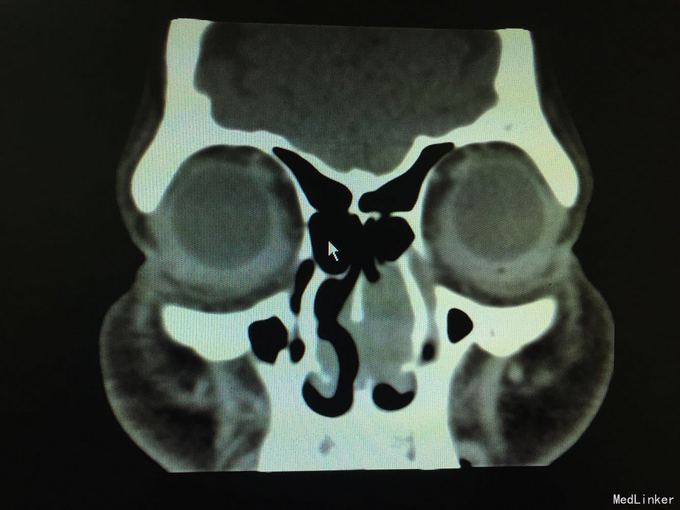

以“间断性左鼻腔出血5月,加重1月”为主诉入院。5月前劳累后出现左鼻腔出血,量中等,可自止,无明显鼻塞、流涕、鼻腔异味,自行口服药物后异味消失(具体药物不详),未正规治疗,1月来左侧鼻腔间断性出血,约3-5天1次,量少,偶浓涕、头晕,无明显鼻痒、喷嚏症状。

查体:双侧鼻腔黏膜充血,左侧总鼻道可见肿物,表面糜烂,质硬,触之易出血,左侧中鼻道窥不及,右侧鼻腔各鼻道未见明显新生物,无活动性出血,鼻中隔偏曲。 增强CT显示肿物内强化明显。

诊断:1.鼻腔血管瘤(左) 2.鼻出血(左) 3.结构性鼻炎 介入手术后3天行低温等离子左鼻腔肿瘤切除术